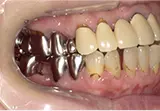

| 年齢/性別 | 40代女性 |

| 主訴 | 右上の詰め物が取れた |

| 治療内容 | 歯周病とむし歯の治療を目的に来院。左下の奥歯は根の状態が悪く、病変も大きかったため保存が困難と判断。 インプラント治療を実施しました。 |

| 治療期間 | 4か月 |

| 費用 | 566,500円税込 |

| リスク・副作用 | 炎症反応によって術後に腫れが生じることがあります。その程度は、手術の範囲や方法によって異なりますが、多くの場合、時間の経過とともに徐々に治まります。 ごく稀に、下顎奥歯の外科手術後に、唇や顎に痺れを感じることがあります。 |